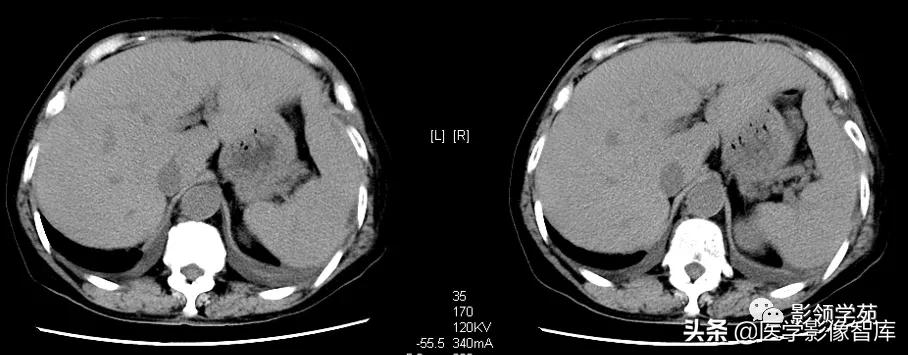

急性期:1)CT平扫:见脾实质内三角形低密度灶,基底位于脾的外缘,尖端常指向脾门,边界清楚或模糊。2)增强扫描:病灶无强化,边界较平扫时更加清楚。